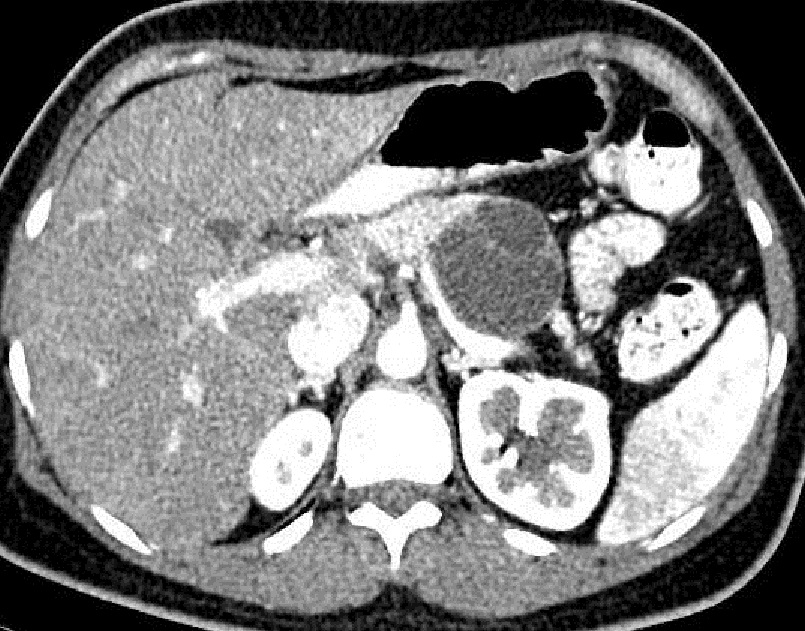

Image radiologique TDM d'une

cystadenome sereux multikystique cephalique du

pancreas a aspect multikystique comporte de plusieur

kyste hypodensite de < 2cm situe a la tete du

pancreas ( fleche rouge ) . Coupe TDM axcilaire |